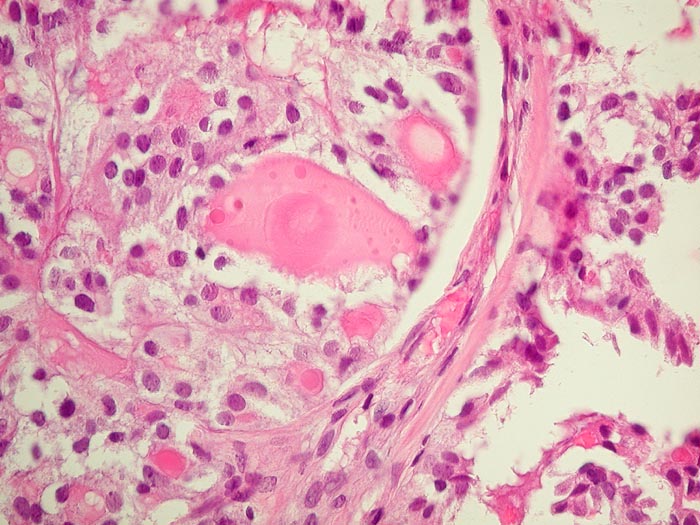

PathoPic ID 2786 - Metastase follikuläres Schilddrüsenkarzinom

Metastase follikuläres Schilddrüsenkarzinom

maligner Tumor

Knochen, Becken

Knochen, Knorpel, Gelenke

Die Metastase zeigt eine Morphologie vergleichbar mit normalem Schilddrüsenparenchym.

Die Tumorzellen reagieren positiv mit Thyreoglobulin sowie mit dem nukleären Transkriptionsfaktor TTF-1

Kein bekanntes Schilddrüsenkarzinom. Vor 30 Jahren Adenokarzinom des Kolons.

Histologie